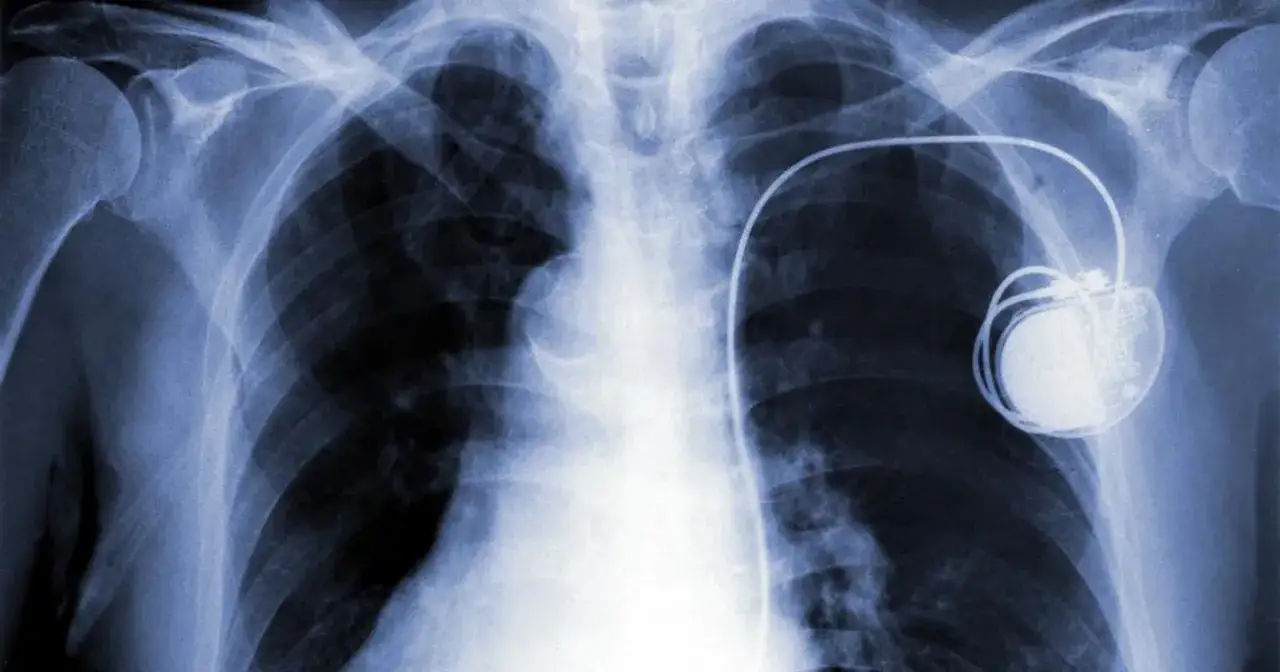

Budowa współczesnego stymulatora serca: Co kryje się w "puszce"?

Ta niewielka "puszka", którą implantujemy pod skórą, to prawdziwe cudo inżynierii medycznej. Zawiera ona nie tylko baterię, ale także skomplikowaną elektronikę sterującą oraz obwody, które generują precyzyjne impulsy elektryczne. Te impulsy są następnie przesyłane do serca za pośrednictwem elektrod, regulując jego rytm. Całość jest hermetycznie zamknięta w biokompatybilnej obudowie, zazwyczaj wykonanej z tytanu, co chroni delikatne komponenty przed płynami ustrojowymi i zapewnia długotrwałą, bezpieczną pracę w organizmie pacjenta.

Proces kwalifikacji do wymiany generatora jest zazwyczaj bardzo płynny, ponieważ opiera się na regularnych wizytach kontrolnych, o których już wspominałem. Podczas tych wizyt lekarz monitoruje stan baterii i, gdy nadejdzie odpowiedni moment (sygnał ERI), informuje pacjenta o konieczności zabiegu. Zazwyczaj nie są wymagane skomplikowane badania. W celu oceny ogólnego stanu zdrowia pacjenta przed zabiegiem, lekarz może zlecić rutynowe badania, takie jak EKG, podstawowe badania krwi (morfologia, elektrolity, parametry krzepnięcia), a czasem zdjęcie rentgenowskie klatki piersiowej. Celem jest upewnienie się, że nie ma przeciwwskazań do przeprowadzenia procedury.